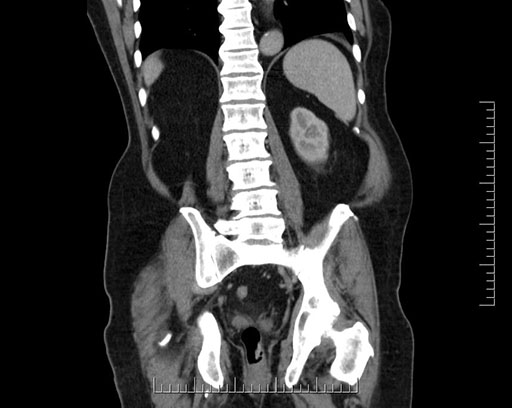

Imaging Analysis

Look through the patient's CT scan to identify any areas of concern for the necessary procedure.

Based on your CT findings, which issue(s) would give reason for "planned slowing down moment(s)" in this case?